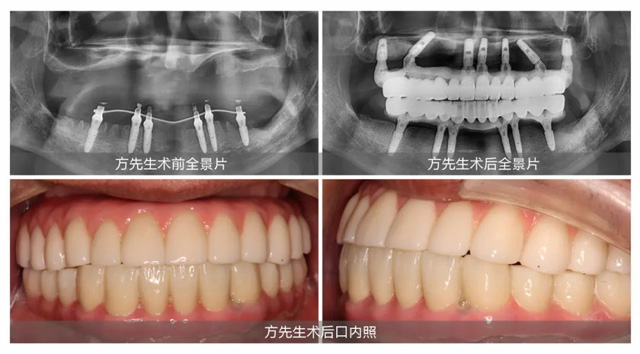

定下方案第三天,方先生在新橋口腔接受了上半口即刻種植。王鋒醫生在方先生上頜同時完成骨粉和7顆種植體植入,當天為他戴上臨時牙冠,成功解決了困擾方先生許久的缺牙問題。成功圓夢的方先生稱贊道:“只有即刻植骨即刻種植,才是真正的好。”